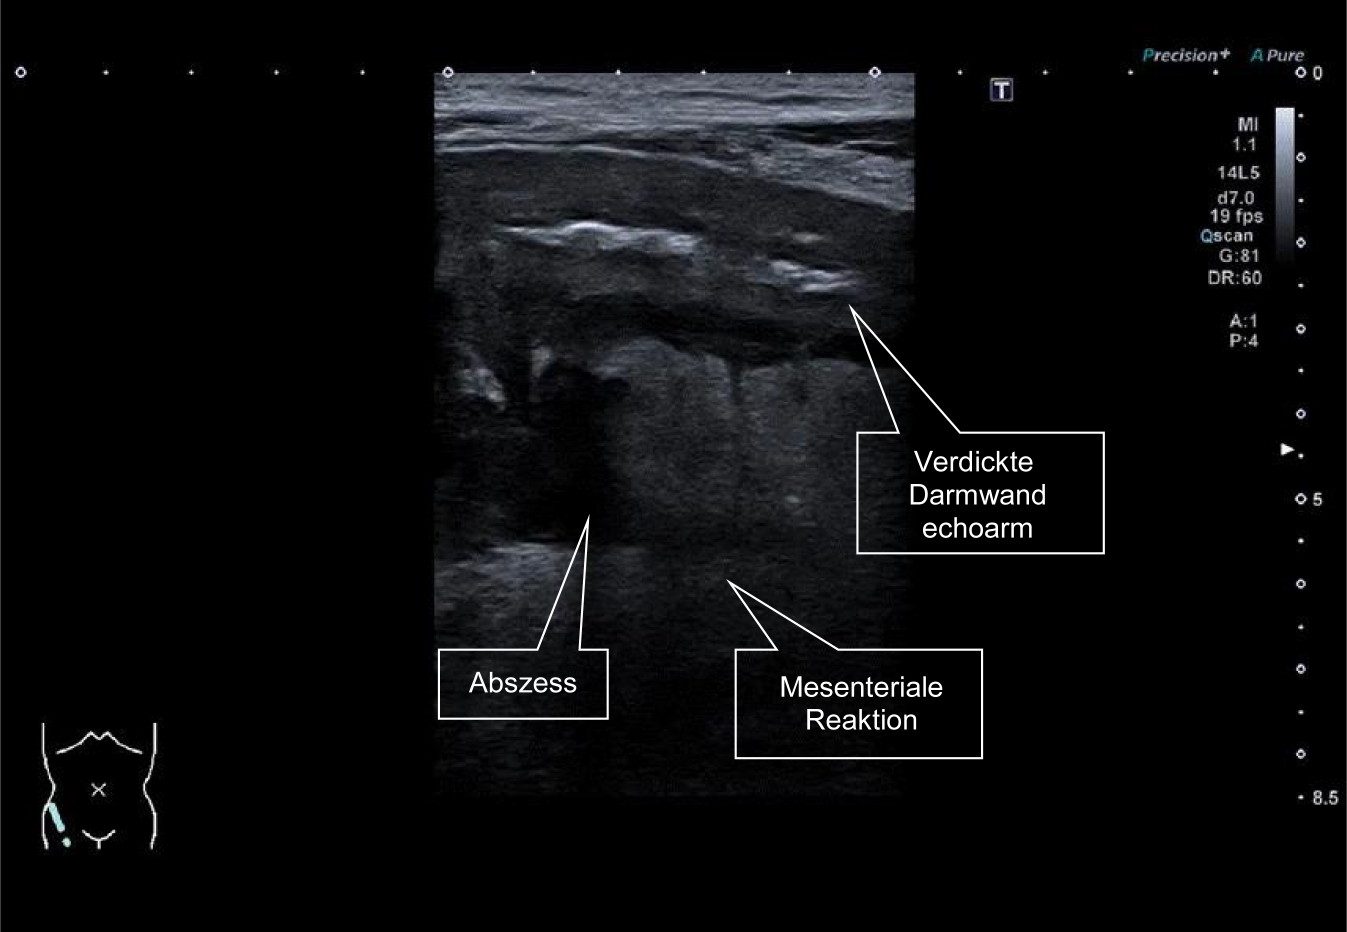

Im akuten Schub der Colitis ulcerosa oder bei chronischer Aktivität zeigt sich ebenfalls eine deutliche Verdickung der Darmwand. Die bei Colitis ulcerosa im Ultraschall sichtbaren Veränderungen sind jedoch keineswegs auf die Mukosa beschränkt. Sehr prominent zeigt sich im Ultraschall des Darms insbesondere eine Verbreiterung der Submukosa. Hier findet sich auch eine verstärkte Vaskularisierung und sicherlich ein Ödem. Ein kontinuierliches, breites Submukosa-Band ist im Darmultraschall typisch für eine aktive Colitis ulcerosa. Bei Morbus Crohn ist im Gegensatz hierzu die Submukosa zwar ebenfalls häufig verbreitert, dies jedoch unregelmässig mit zum Teil echoarmen Arealen, die vermutlich einem Entzündungszellinfiltrat in die Submukosa entsprechen (Abb. 7).

Abb. 7

58-jähriger Patient mit seit 18 Jahren bekannter Colitis ulcerosa. Nach 5 Jahren in Remission unter Vedolizumab neu aufgetretene blutige, schleimige Durchfälle nach COVID-19-Infektion. Das Sigma deutlich wandverdickt mit prominenter Submukosa bei erhaltener Stratifikation. Mesenteriale Mitreaktion als Zeichen einer deutlich aktiven linksseitigen Colitis ulcerosa. Die typische Gasfüllung im Sigma fehlt fast vollständig